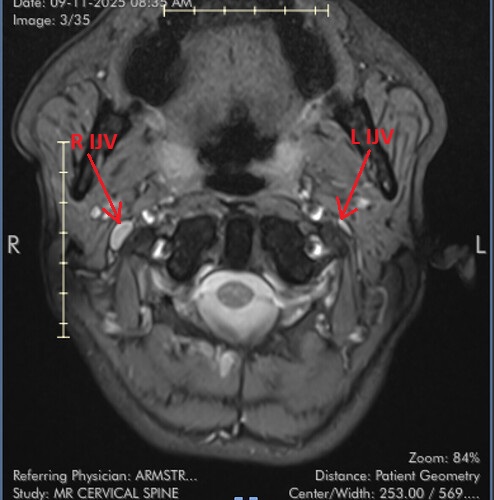

I marked the images for you and marked the IJV.

So you can see how the IJV passes by the transverse processes of C1 which are compressing. In this position the right IJV does not have severe compression, but in Figure 2 you can see that the left IJV is almost invisible, and in the other images there is significant narrowing.

On MRI, it is very difficult to see the styloid processes.